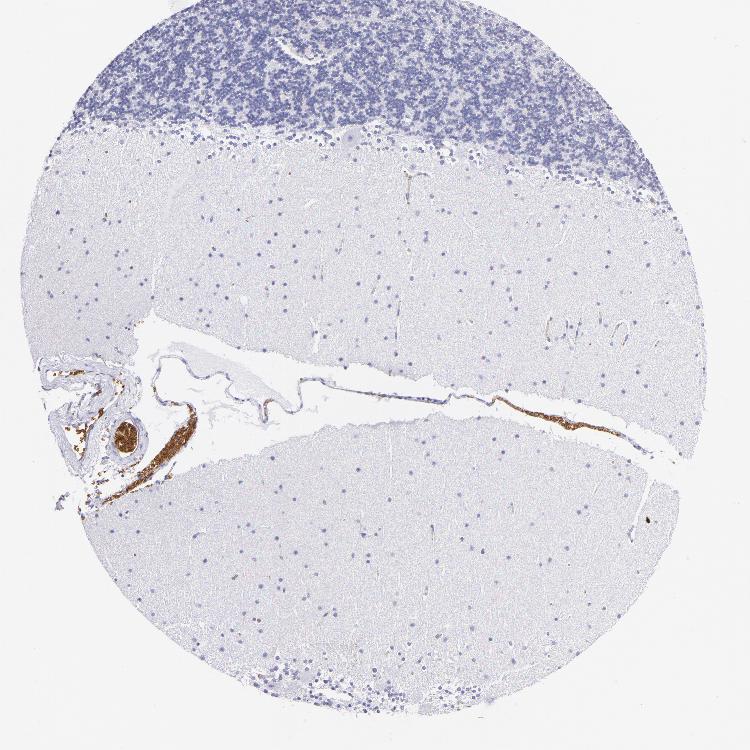

BRAIN CEREBELLUM Show tissue menu

CEREBELLUM - Expression summary

CEREBELLUM - Antibody stainingi

Antibody staining in the annotated cell types in the current human tissue is reported as not detected, low, medium, or high, based on conventional immunohistochemistry profiling in selected tissues. This score is based on the combination of the staining intensity and fraction of stained cells.

Each image is clickable and will lead to virtual microscopy that enables deeper exploration of all samples and also displays staining intensity scores, fraction scores and subcellular localization as well as patient and tissue information for each sample.

Antibody HPA014811Antibody CAB002658

Purkinje cells Not detectedNot detected

Cells in granular layer Not detectedNot detected

Cells in molecular layer Not detectedNot detected